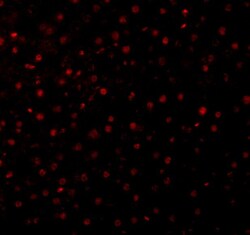

- Immunofluorescence of Caspase-12 in Mouse Liver cells with Caspase 12 Polyclonal Antibody (Product # PA5-19963) at 10 µg/mL.